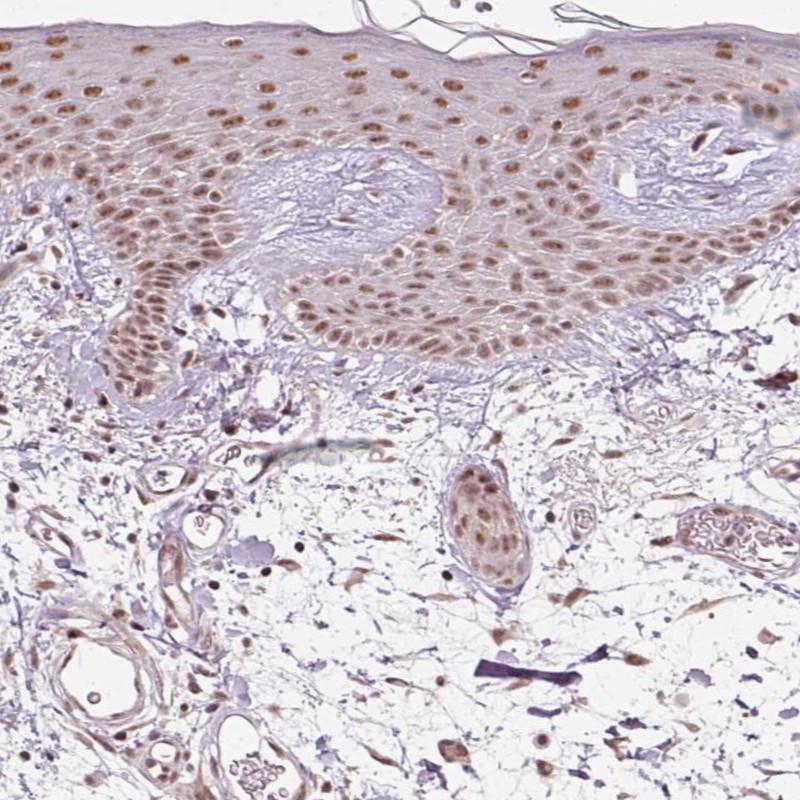

Immunohistochemical staining of human skin shows moderate nuclear positivity in keratinocytes.